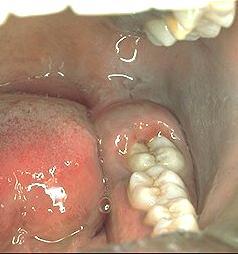

- Pericoronitis (inflammation of soft tissues around the crown of a partially erupted tooth, most commonly seen in association with the lower wisdom teeth)

The space between the crown of the tooth and the overlying gum flap (operculum) is an ideal area for the collection of bacterial plaque and food debris, leading to inflammation (pericoronitis).

Swelling from the inflammation increases the chance of trauma from the opposing teeth and aggravates the inflammation. Wisdom tooth pericoronitis is often a recurrent problem if the main cause is not removed.

Wisdom tooth inflammation (pericoronitis) symptoms

- Swelling, redness and soreness in the gum flap